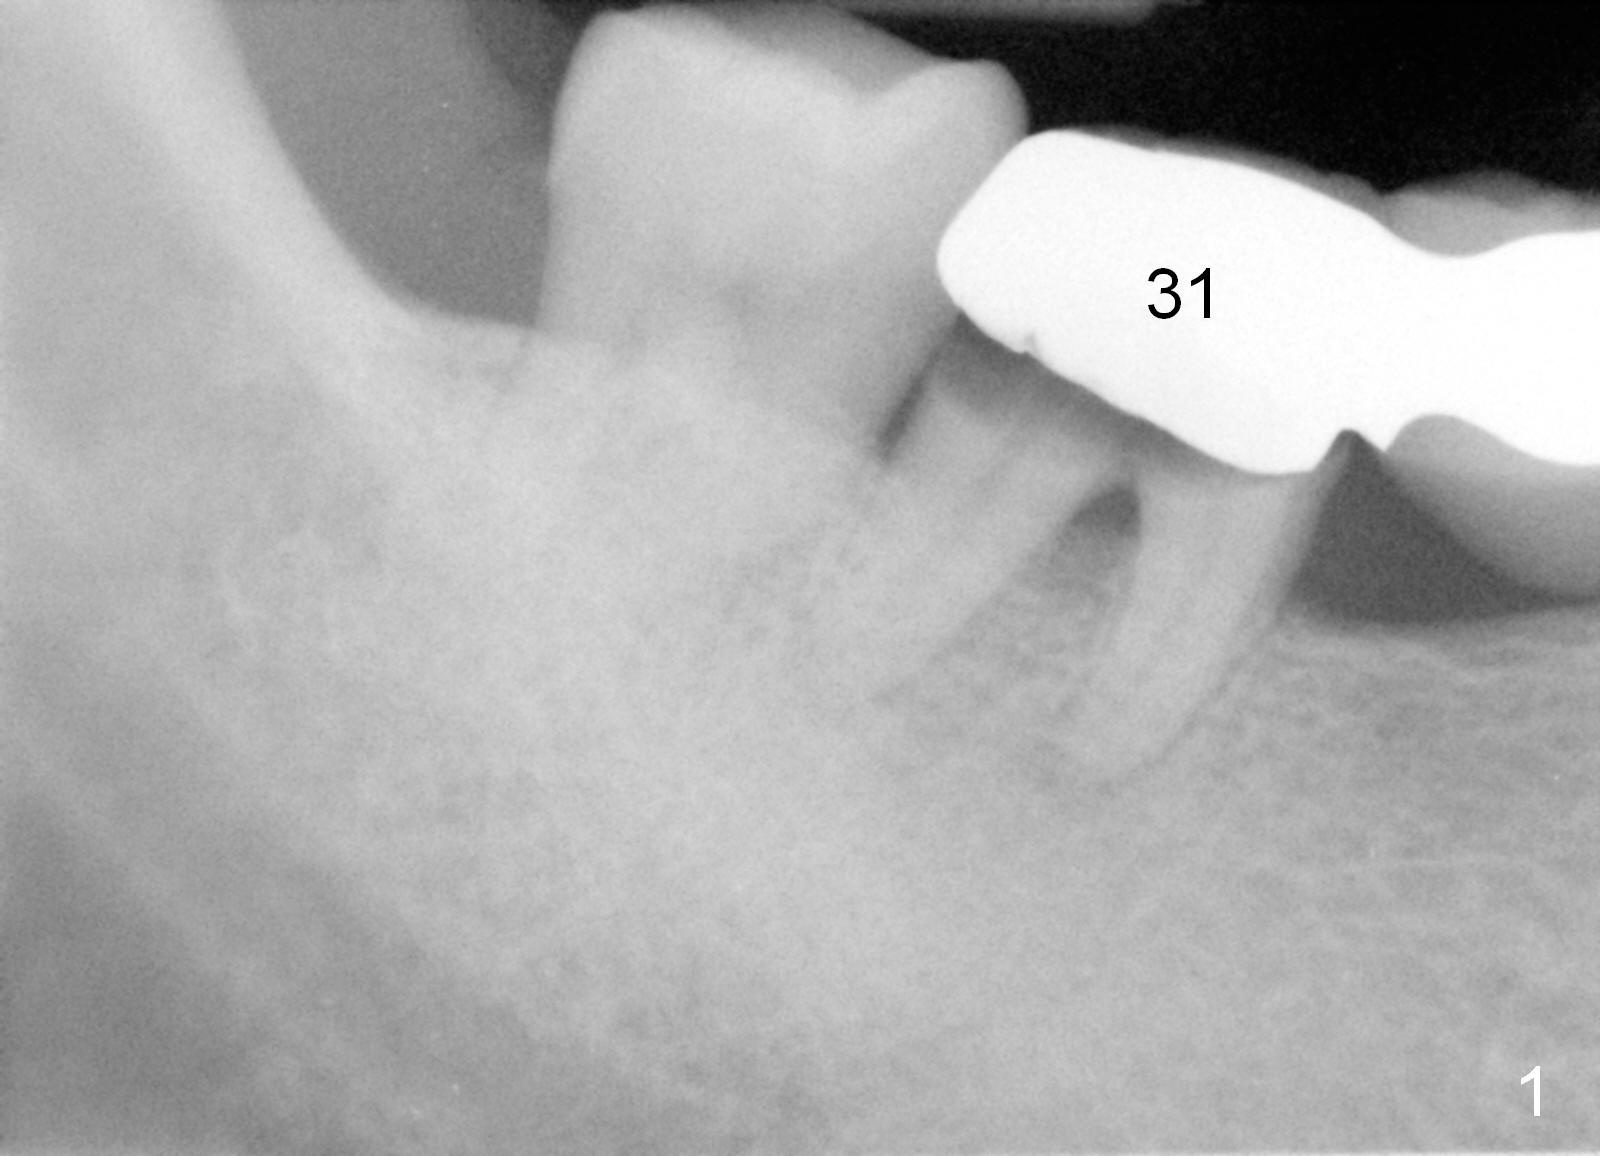

A 47-year-old man works in Africa.  While he is visiting his family at Atlanta, he has toothache in the lower right.  Examination reveals secondary caries under #31 retainer (Fig.1) and mesial open margin of #28 retainer (Fig.2).  Surgery is scheduled next day.